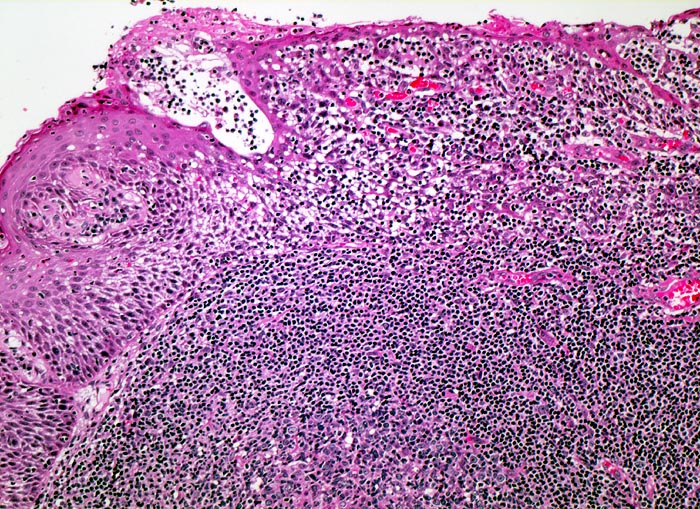

Lymphknoten, lymphatisches Gewebe des Oropharynx und Tonsillen zeigen ähnliche Veränderungen:

• Aktivierung der B-Lymphozyten-Areale (EBV induzierte polyklonale Infektion und Stimulation der EBV-Rezeptor tragenden B-Zellen): grosse, aktivierte Keimzentren (=follikuläre Hyperplasie), aktive parafollikuläre Plasmazellbildung (B-Immunoblasten, Plasmoblasten, Plasmazellen).

• Aktivierung der interfollikulären T-Zone (= sogenannte bunte Pulpahyperplasie) mit Hodgkin-artigen Zellen (= reaktive/aktivierte B- resp. T-Lymphozyten).

Beim Auftreten von Reed-Sternberg-artigen Zellen kann die morphologische Abgrenzung von einem Hodgkin Lymphom sehr schwierig sein.

• Follikuläre Hyperplasie:

Reaktive Keimzentren mit Zentrozyten, grösseren Zentroblasten und Kerntrümmermakrophagen. Follikel mit dunkler Mantelzone.

• Interfollikuläre Hyperplasie der T-Zone (bunte Pulpahyperplasie):

Hodgkinartige Zellen (=reaktive/aktivierte B- resp. T-Lymphozyten), kleine Lymphozyten, Immunoblasten mit zentralem Nukleolus und Plasmazellen.